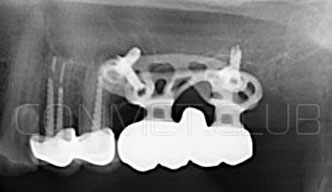

2. После этого произвели компьютерное моделирование самого имплантата и фиксирующих элементов. Примечательно, что в абатментах, использовался отлично зарекомендовавший себя и проверенный десятилетиями интерфейс КОНМЕТ! В результате получили несколько специальных файлов, позволяющих не только сделать сам имлантат, но еще до операции изготовить и сами зубы. Данные файлы передали в изготовление на специальном 3D оборудовании.

Сама же операция длиться 20-50 минут в зависимости от количества утраченных зубов. В процессе этой операции, после проведенной местной анестезии, делается разрез на слизистой, она приподнимается и субпериостальный имплантат укладывается на кость. После этого рана фиксируется несколькими швами и все! Через 10-14 дней мягкие ткани срастаются и надкостница надежно удерживает имплантат на месте. Нет необходимости ждать несколько месяцев, как это бывает в случае с внутрикостными винтовыми имплантатами.

Новые, искусственные зубы фиксируются к этому имплантату стандартными, трансокклюзионными винтами на 1-14 день (в данном клиническом случае на 5 сутки) и по существу являются несъемными!

Первый вывод к которому мы пришли, это то, что для данных конструкций имплантатов сохранять внутренний интерфейс с шестигранником и конусом Морзе нецелесообразно из-за ограничения возможностей современной 3D печати титана. Кроме того, техническая обработка после 3D печати такого интерфейса представляет значительные трудности и ведет к неоправданному увеличению цены. Поэтому пришли к единодушному мнению, что лучший вариант-это опорные элементы полностью повторяющие абатменты-мультиюниты.

Результаты проведенных в 2017-2018 году операций субпериостальной имплантации показали их высокую эффективность, очень быструю адаптацию пациентов к новым зубам и отсутствие послеоперационного болевого синдрома. Интересной особенностью является труднодиагносцируемая, но точно присутствующая микроподвижность имплантатов спустя 6-12 месяцев. Учитывая данную особенность надо категорически избегать объединения субпериостальных имплантатов с естественными зубами или внутрикостными имплантатами!